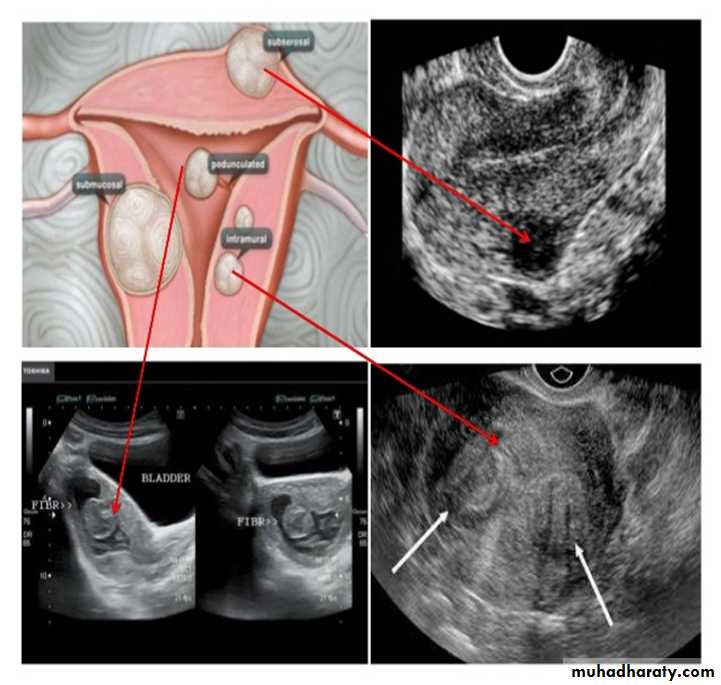

Uterine fibroid